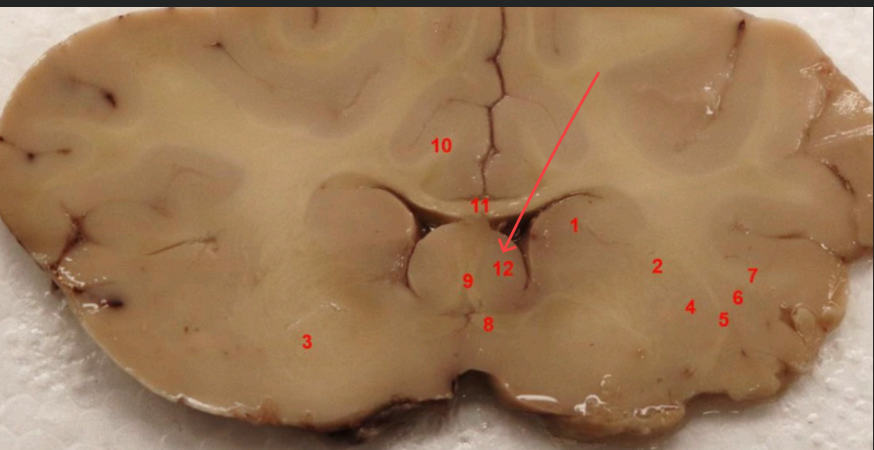

what area is this?

Denate Gyrus

what is this

Habenula

fornix

mammillothalmic tract

what area is this

hippocampus

entorhinal cortex

subiculum

lateral geniculate nucleus, filters visual signals, mediates attention by prioritizing important information,

what is this (13)

hippocampal commisure

LGN

enthorinal cortex

MGN

thalamus

posterior commissure

splenium of corpus callosum

superior colliculs

cerebral aqueduct

periaqueductal gray

superior colliculus

red nucleus

what is this, function

ventral tegmental area , brain's reward system, motivation, and emotion regulation

substaina nigra, regulates voluntary movement, motor planning, reward-seeking, and addiction

cerebral punducle

what is this, function?

dorsal raphe nucleus , serotonin, (mood, sleep, emotion)

what is this , function

locus coerules , regulating arousal, wakefulness, attention, and stress responses

dorsal raphe nucleus

superior cerebellar punudcle, inferior cerebellar punducle

what is this , function?

Reticular formation arousal, consuoiunsess, sleepwake ( keeps u awake!!!)